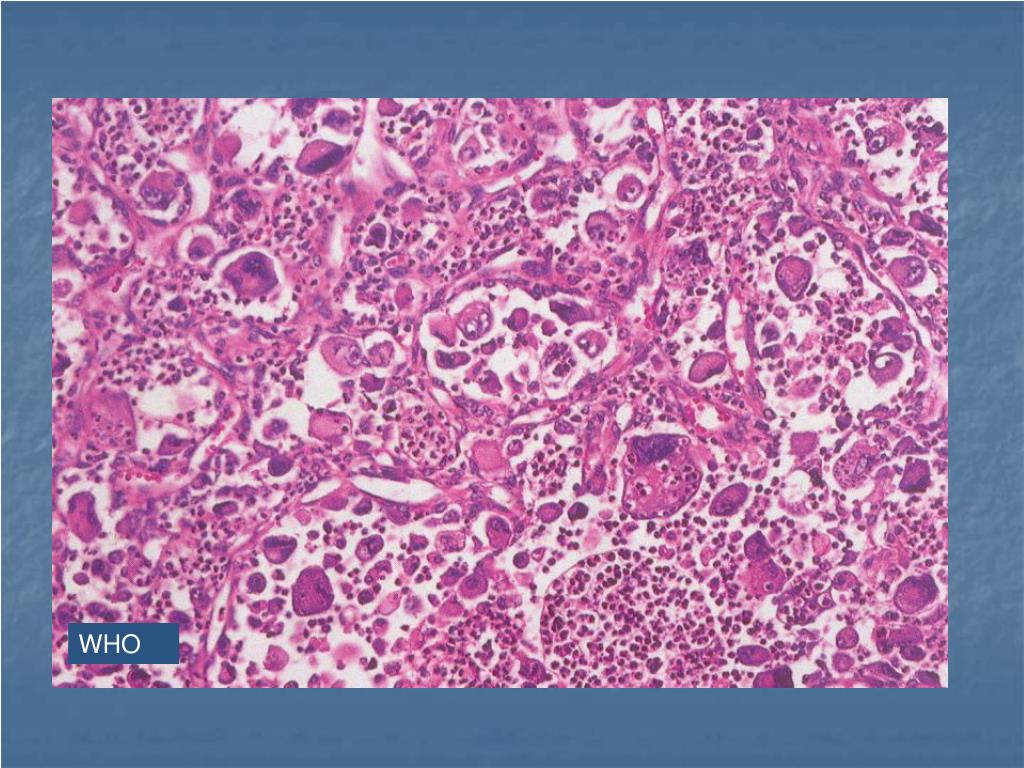

19. WHO

20. WHO

21. WHO